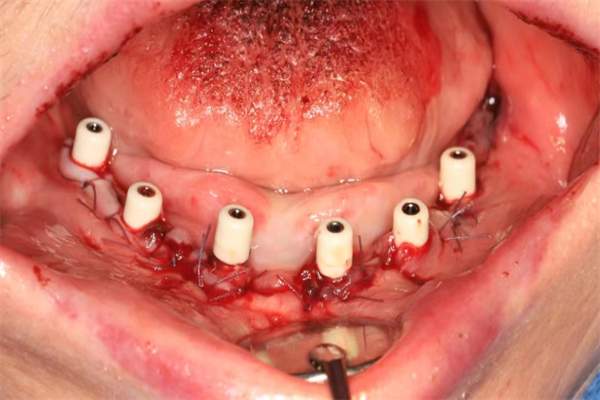

手術(shù)當(dāng)天,楊濤主任和王可醫(yī)生在麻醉科的協(xié)助下,整個拔牙及種植過程十分順利。術(shù)后X線片顯示,種植體的植入深度、角度,高度都非常精準(zhǔn)。

術(shù)后X線檢查,確認(rèn)種植體植入位置